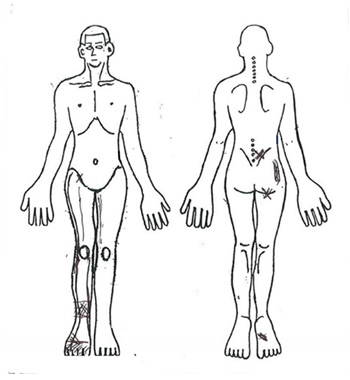

- Chief complaint

- Numbness and pain in the right hip to lower limb when walking, walking disorder.

Figure 2-3. Symptoms in the hip and lower extremities.

- Symptom: Pain in the lower leg at the bile meridian (meridian on the outer side of the lower limb) during right oblique forward bending of the lumbar region.